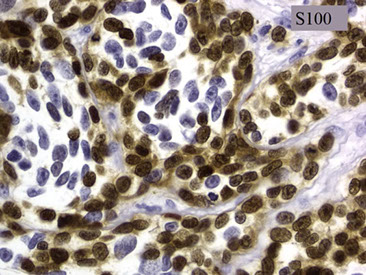

Expression of annexin A1, DBA-44, and BCL1 by hairy cell

leukemia (HCL). This HCL is the same case shown in Figure 4.A through C, The atypical lymphoid cells are positive for annexin A1 (partial) (A), DBA- 44 (B), and BCL1 (partial) (C) (original magnification3400 [A]; original magnification x200 [B]; original magnification x200 [C]).

IHC: TRAP is a technically difficult stain to perform

(+) CD20/22/11c/103/25/123, T-bet, annexin-1 (ANXA1), DBA.44, FMC-7, Cyclin D1 (weak), HBME-1, cyclin D1 (weak, and does not harbor the genetic mutation)

(-) CD5 / 10 (+ in 10-20%)/ 23 / 43

Should have the ABCs of HCL to distinguish from mimickers: Annexin A, BRAF and Cyclin D1